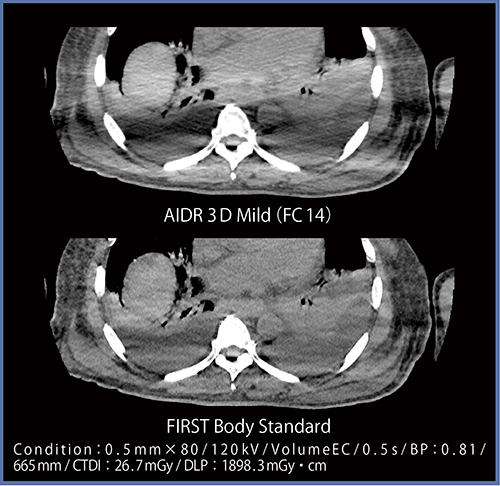

FIRSTではアンダーシュートが低減され,のっぺりした印象となるため,導入当初はAIDR 3Dとの見え方の違いに戸惑うこともあった(図1)。また,FIRSTでは,骨の表面がややザラザラとした画像となるものの,VR画像は分解能を保持したまま作成でき,CPR画像はウインドウ変更のみで脊髄など軟部組織の観察が容易となる(図2)。

図1 症例1:腰椎骨折(どちらもWW,WLは同じ。図2〜11も同様)